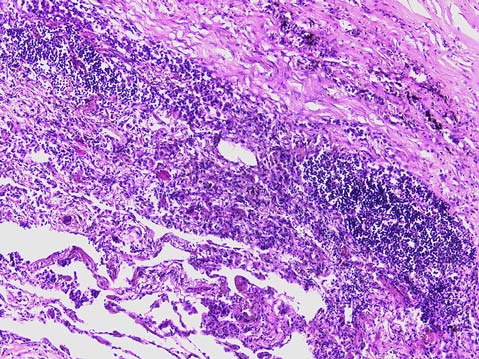

При патологоанатомическом вскрытии в левой плевральной полости около 1200,0 мл тёмно-красной крови, в виде сгустков и в жидком состоянии. Лёгкие тестоватой консистенции на всём протяжении, на разрезах лёгкие светло-красного цвета, с поверхностей разрезов при сдавливании стекает значительное количество пенистой жидкости. В правом лёгком в верхней доле находится очаг уплотнения диаметром до 5 см, белесоватого цвета. При гистологическом исследовании выявлена гумма, представленная очагом казеозного некроза с периферической диффузной и очаговой воспалительной инфильтрацией преимущественно из плазмоцитов, макрофагов, лимфоцитов, склерозом, признаками эндоартериитов (рис. 1, 2).

Рис. 1. Гумма в лёгком: очаг казеозного некроза, окружённый валом из воспалительных клеток. Окраска гематоксилином и эозином. Увеличение ×50

Рис. 2. Гумма в лёгком: вокруг очага казеозного некроза воспалительный инфильтрат из лимфоцитов, макрофагов, плазмоцитов, эндоартериит. Окраска гематоксилином и эозином. Увеличение ×200